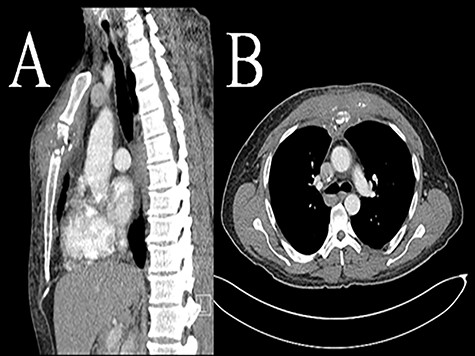

Primary infection is rare with exact incidence not known. Since first reported in 1976 up until 2019, there have been 14 case reports of sternomanubrial joint infections with a total of 19 patients. Thirteen of these cases are in adults while one paper has described six cases in children [6]. The most common etiology is methicillin-sensitive Staphylococcus aureus. There is only one previous paper that has described this disease in IVDU [7]. The underlying risk factors are the same as any other septic arthritis i.e. immunosuppression, steroid use, antimetabolites, concomitant infections distant from the sternomanubrial joint and Mycobacterium tuberculosis [4–8]. Pain and swelling over the joint are the most common presenting symptoms. Sometimes, the presentation can be delayed [3]. Fever and leukocytosis are not always present. Diagnosis is based on physical exam and confirmed with imaging using computed tomography (CT scan) or magnetic resonance imaging (MRI). If abscess is found on imaging, joint aspiration can also be performed to help direct preoperative antibiotic treatment (Fig. 1).

Computed tomography (CT scan) sternomanubrial joint bone erosion and phlegmon. Computed tomography (CT scan): A (sagittal view) and B (axial view).